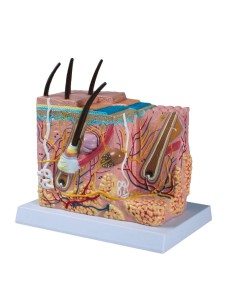

Scopri il Mondo dell’Anatomia con Modelli anatomici di Precisione

Modelli Anatomici Dettagliati per Ogni Necessità

Dal cranio in 22 parti con incastri magnetici ai modelli di colonna vertebrale, da quelli di articolazioni a quelli di cuore, ogni pezzo della nostra collezione è progettato per un’immersione totale nello studio dell’anatomia umana. I nostri modelli, realizzati tramite scansioni di ossa vere, garantiscono un’esperienza tattile autentica e una fedeltà di peso quasi identica agli originali.

Strumenti Didattici Innovativi per l’Educazione e la Pratica Medica

Essenziali per studenti e professionisti, i nostri modelli anatomici sono strumenti didattici che permettono di osservare le strutture anatomiche con precisione, eliminando la necessità di dissezioni o studi invasivi. Sono inoltre utili per spiegare ai pazienti le patologie, rendendo la comunicazione più efficace e risparmiando tempo prezioso.